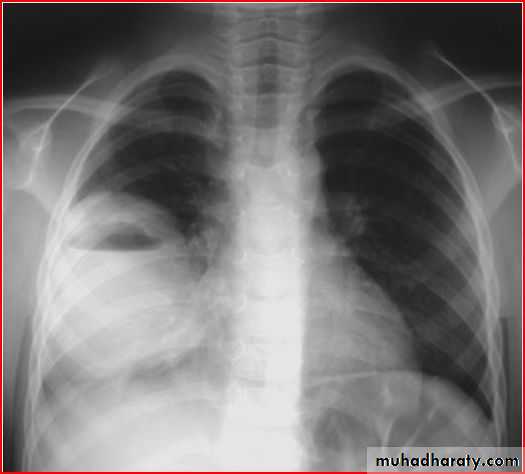

monliasiscardiomegaly

globular heart pericardial effusion

pleural effusion - multiple opacities

TB ddxheart cardiomegaly و pleural effusion

May with periphral lymph adenopathyNormal ECG

dextrocardia with situs inversus